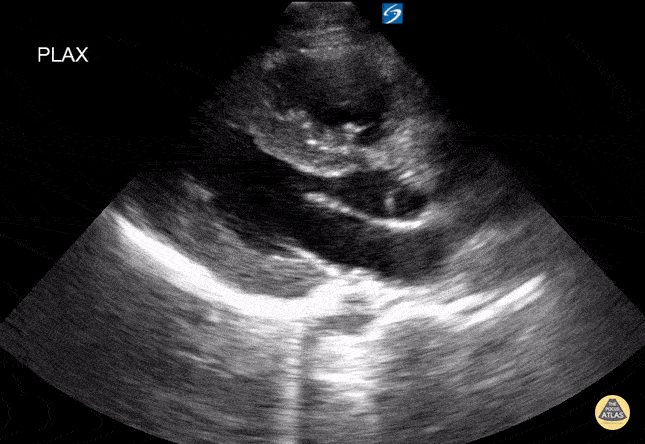

15 year old with chest pain. POCUS shows left ventricular hypertrophy. Referred to cardiology after normal labs. Contributor: Kathryn Pade, MD